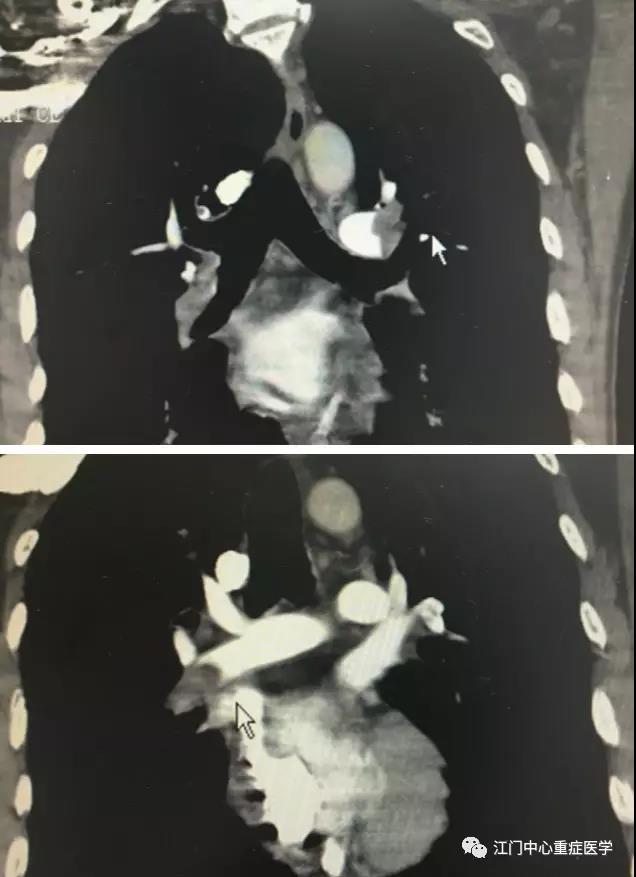

而实时的肺动脉三维螺旋CTA图像也印证了郑医生的观点。李师傅的肺血管被狠狠堵死,造成呼吸不好、血管不通,他只有40%的生存可能。

经历了一夜的漫长守望,伴随着西江的旭日东升,李师傅病情得以改善,神志转清,呼吸、血压好转,再次复查肺动脉CTA,肺动脉栓塞的程度明显减轻,这也意味着生命的通道重启了。郑医生看完CT图像,揉了揉眼睛,终于放下了心头大石。